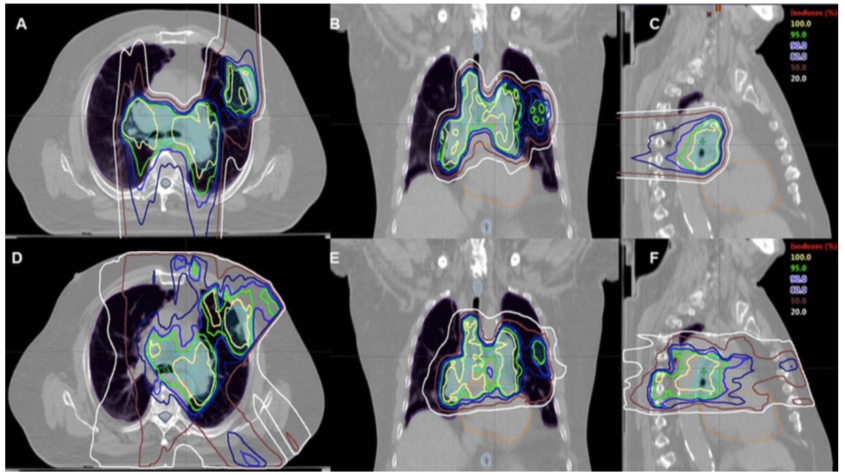

示例:74岁女性患者,局限期小细胞肺癌,累及右肺下叶、右肺门,伴纵隔淋巴结转移。质子治疗计划的轴向图(A)、冠状图(B)和矢状图(C)。 (D–F)为相应的IMRT治疗计划图。计划靶区(PTV)以青色显示。

在14个月的中位随访时间中,1年和2年局部控制率分别为85%和69%;中位总生存期为28.2个月,1年和2年总生存率分别为72%和58%。各有1例患者(3.3%)发生了3级或以上食管炎、肺炎、厌食症、心包积液,2级肺炎和食管炎的发生率分别为10.0%和43.3%。与IMRT备选治疗计划相比,质子治疗计划显著改善了心脏、脊髓、肺V5和平均肺照射剂量。质子治疗在这项研究中具有理想的疗效和毒性反应。ccQ帝国网站管理系统